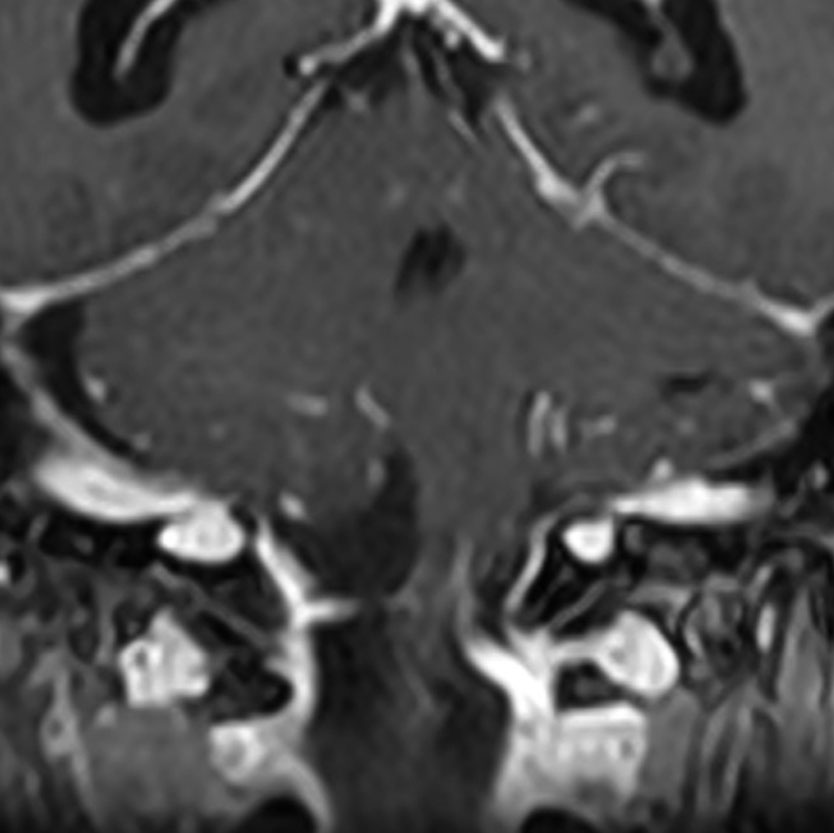

大後頭孔(大孔)髄膜腫 foramen magnum meningioma)

この腫瘍はfarlateral approachなどの頭蓋底手術をしなくても,外側後頭窩開頭で全摘出できます。要領は,S状静脈洞の下端の周囲骨を削除することです。大後頭孔髄膜種は延髄を圧迫するので巨大なものはありません。出血のコントロールや延髄からの剥離は比較的容易なものが多いでしょう。舌咽神経と迷走神経損傷を避けることが重点となります。

迷走神経と舌咽神経は機能温存できました。舌下神経が腫瘍の表面に薄く広がり剥がすことができずに半分以上を切断しています。でも片側舌下神経麻痺では日常生活に困ることはあまりありません。